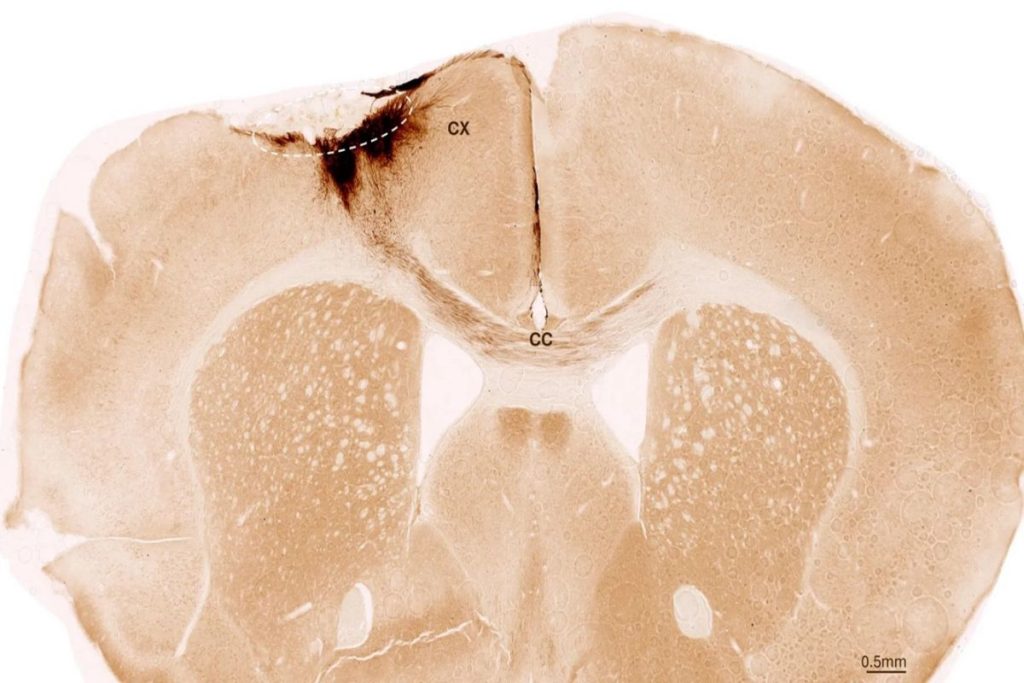

Μεταμοσχεύτηκαν νευρικά βλαστικά κύτταρα σε ποντίκια και πέτυχαν αναγέννηση των κατεστραμμένων νευρώνων τους, αποκατάσταση της κινητικότητάς τους και «επιδιόρθωση» των πληγέντων αιμοφόρων αγγείων τους – Ανοίγει ο δρόμος και για τους ανθρώπους